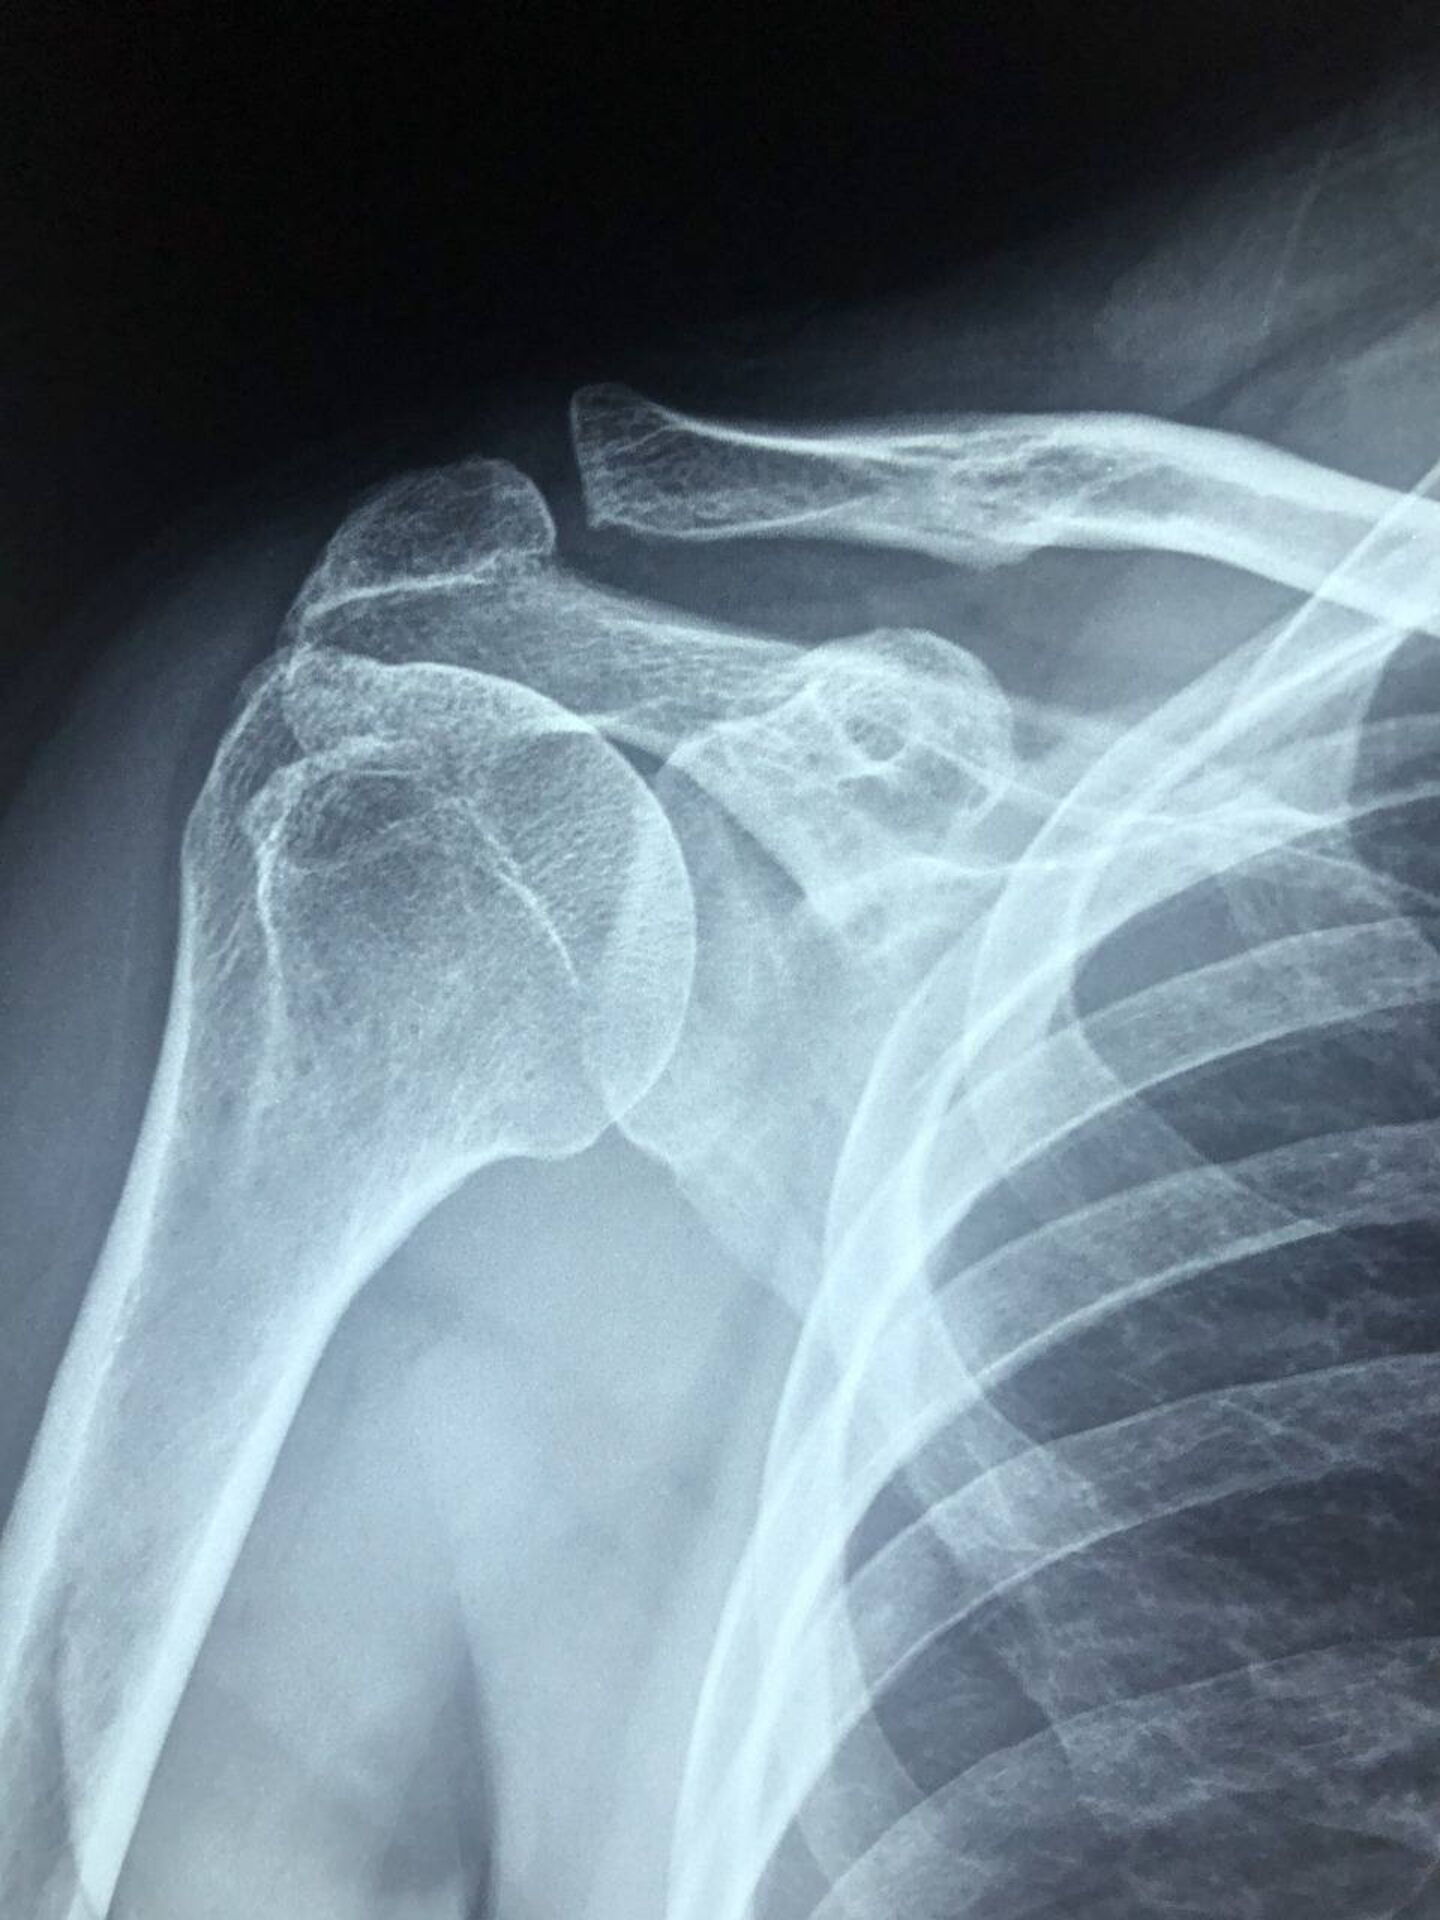

L’absence de PV d’enquête de Police profite à un motard victime d'une fracture de la malléole lors d'un accident de la route à Marseille.

La victime d’accident de la route en moto à Marseille a droit à la réparation intégrale de son préjudice corporel, sauf si une faute de conduite peut lui être reprochée, sur la base des dispositions du code de la route. La compagnie d’assurance en charge de l’indemnisation du motard victime d’acc...